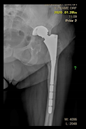

Figure 2.

Design steps of the aiming device: (a) Stemmed acetabular cup with guiding wire; (b) drawing of the guiding sleeve and the reference points; (c) connection of the reference points and the guiding sleeve; and (d) adjustment of the handle.

Next, the aiming device was designed, starting with the guiding sleeve. Its length was typically 60–70 mm, which provides appropriate guidance. However, this length is influenced by the position of the femur, which can be seen in the 3D reconstruction. Even with a diameter of 10–12 mm, the guide wire is safely targeted (Figure 2b). A chamfer of 1–2 mm around the inlet surface of the guide cylinder ensures that no cutting edge is formed at the boundaries of the surfaces. On the outlet side, also chamfered, was left 2–3 mm from the bone surface, thus avoiding the possibility of the guide stem accidentally resting on the surface of the shaft, thus altering the aiming direction. In the early versions, the targeting body adopted the unique shape of the damaged side of the hip, with a groove for the index finger to help hold it in position. In practice, however, it proved difficult to drill and hold the finger in a safe position at the same time. Furthermore, it was found to be problematic when the targeting device was in contact with the bone over a large surface area. The accuracy of the 3D reconstruction and the preparation of the hip may have had a negative effect on the direction of the targeting device in the event of large surface contact and, thus, the accuracy of aiming. These observations led to further development. Later practice was to position the target with three reliable bony sections. Once the support points were designated, slots were constructed between the designated points and the central part of the device. A hexagonal and a triangular socket was constructed to replace the finger positioning. A stainless-steel hand tool was used to retain it in position. However, the hand tool that was used limited the space available for the drilling tool, making it difficult to use the targeting device.

Our previous practice was to use three reliable bony formations to position the aiming device, but experience has shown that these can break off during surgery. However, in addition to two titanium screws, a third point on the lower bony frame provided a secure three-point fixation. For the ideal adjustment of its position, the support arms ending in 12 mm diameter spheres wrapped around the head of the two reference screws, and the third one touched a reliably solid part of the lower edge of the bony acetabulum. The edited spheres, using a Boolean subtraction operation, take the shape of the selected periacetabular bony anatomical point on the anterior margin of the defective acetabulum and the screw heads. Grooves were created in the spheres for the screw heads, considering the need to be able to remove the targeting device after drilling while keeping the guiding wire in position.

These three reference points were linked to each other and to the guide sleeve by means of suitably designed connecting profiles. It was considered that these reference points would be deep and difficult to reach during the operation, so the aiming cylinder of the guiding wire and the spheres around were connected by means of half-toroids of 50–60 mm diameter, considering bypassing the soft tissue (Figure 2c). In the last, fourth version, to replace the hexagonal and triangular sockets, a handle was added to the aiming device outside the skin surface (Figure 2d).